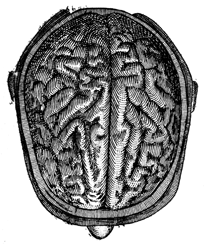

Chapter II—Structure of the Brain.

convolutions differs from their actual appearance—View of the superior

surface illustrated—Difference between the irregular convolutions

and the angular maps—View of the inferior surface of the